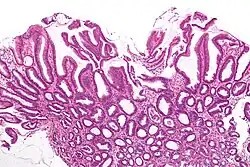

| Micrograph of a reactive gastropathy. H&E stain. | |

- Foveolar hyperplasia (black arrow), as a tortuosity in the "neck" region of the gastric glands.

- Scant or minimal inflammatory cells (white arrow), i.e. lack of large numbers of neutrophils and plasma cells..

- Smooth muscle hyperplasia in the lamina propria (in black oval).

The diagnosis is by examination of tissue, e.g. a stomach biopsy.

High mag.